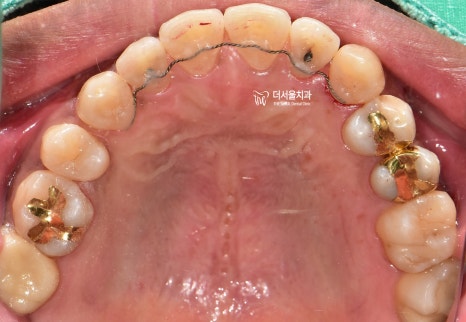

이건, 교합면에서 봤을 때

더 명확히 드러나게 됩니다.

상악 악궁에 배열 된 치아들은,

살짝 한쪽으로 쏠려 있는 것을 볼 수 있습니다.

어금니의 위치는 서로 대칭이 되는데,

앞니쪽으로 갈 수록 악궁의 형태가

조금 비대칭이 되는거죠.

발치를 결정할 수 밖에 없었고

양측으로 동시에 발치를 하는게 아닌,

#14, 44번 치아만 발치하는

편측발치로 진행을 하게 될 상황입니다.